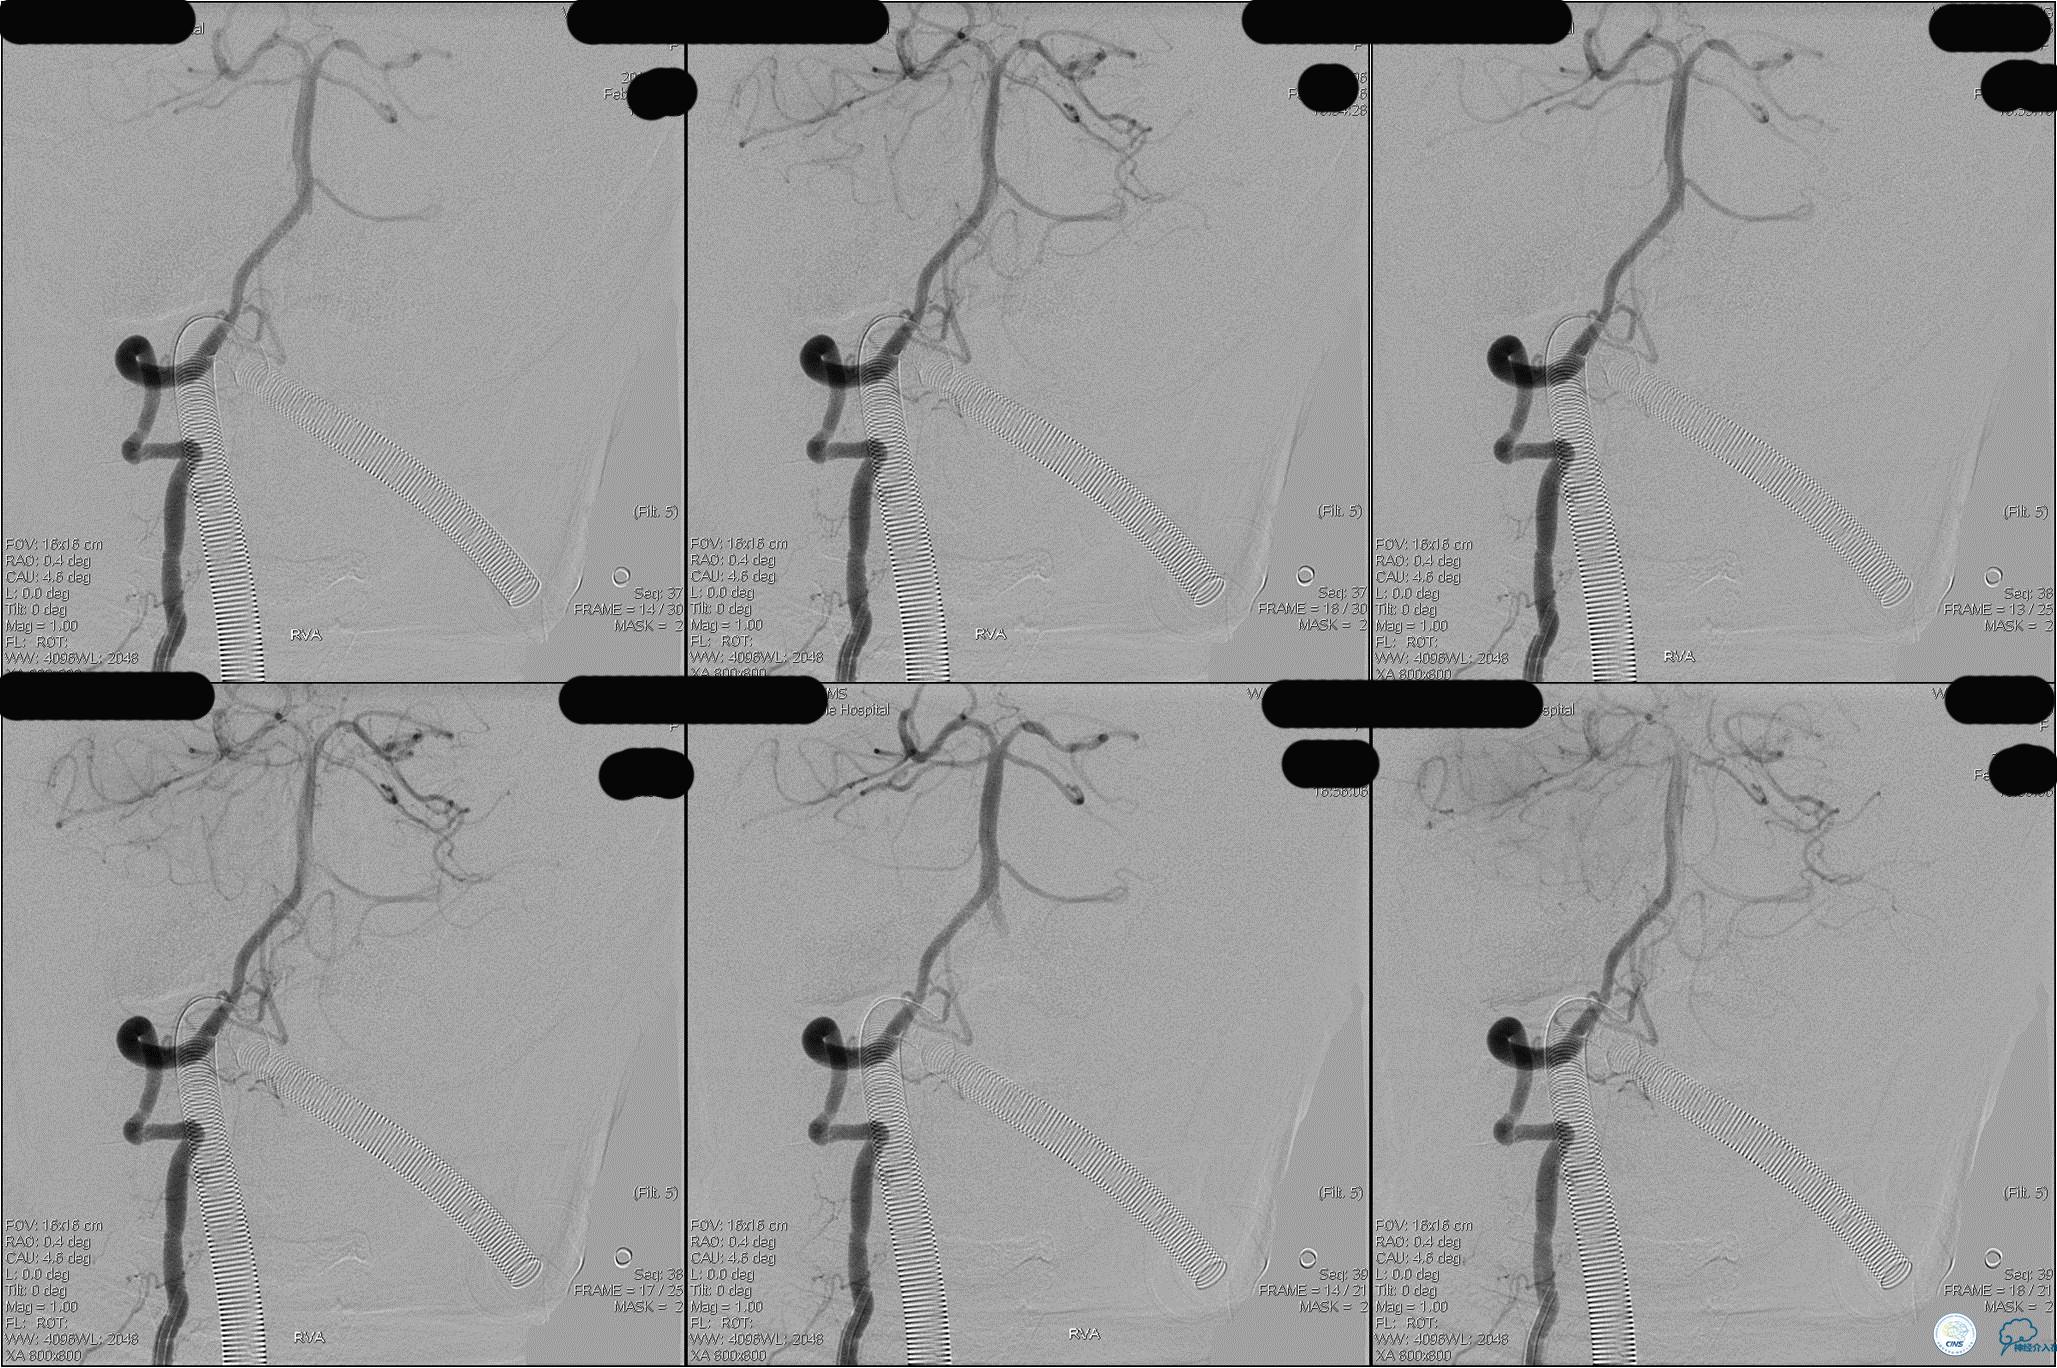

》DSA资料(第3次取栓后,发病10h)

》DSA资料(观察30min后,左椎造影)